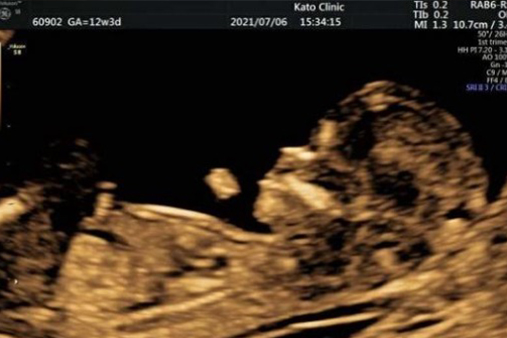

妊娠初期胎児スクリーニング(胎児ドック)は、超音波検査(エコー検査)によって染色体異常のリスクを推定する検査です。一般的な妊婦健診での超音波とは診るポイントが異なり、より詳細に観察することで、胎児がもつ可能性のある病気のリスクを評価します。

妊娠初期胎児スクリーニングでは、胎児超音波の専門産婦人科医がNT(首の後ろのむくみ)を含む超音波マーカーを計測し、専用のソフトウェアを用いてリスクの確率計算を行います。具体的には、以下の項目を計測します。

NTや胎児の発育状況などから、21トリソミー、18トリソミー、13トリソミーの可能性を推定します。ただし、超音波画像をもとに判断するという検査の特性上、見た目ではわからない疾患については判定することができません。また、赤ちゃんの体勢によっては十分な観察ができない場合もあります。